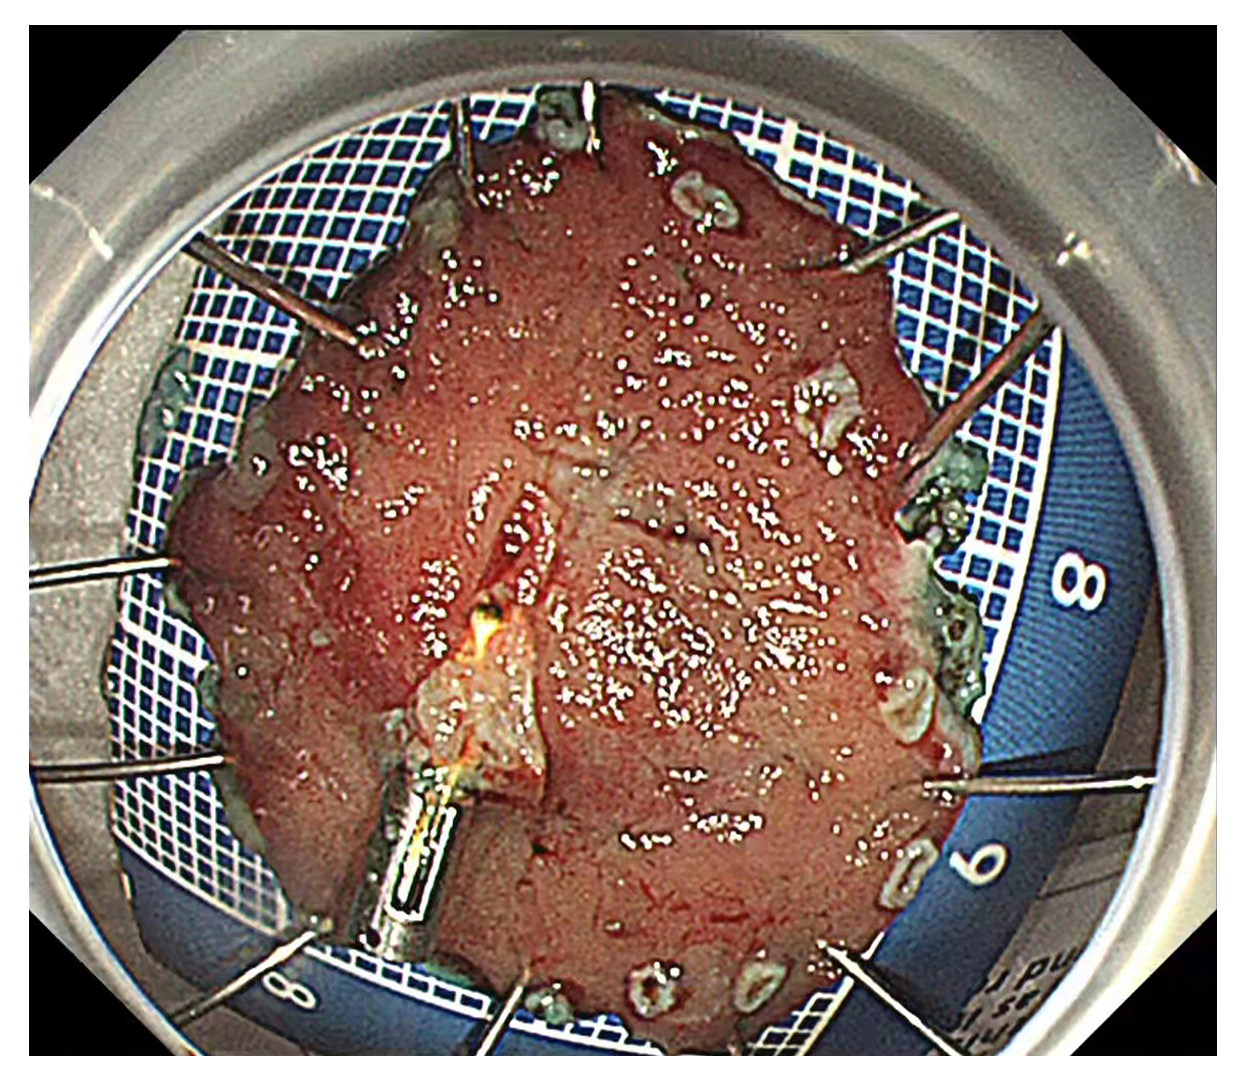

内镜中心独立完成了多例食管、胃、结肠早癌完整切除术,并成功开展了食管良性狭窄切开术,间质瘤挖除术,食管癌伴食管狭窄支架置入术,消化道异物取出术,痔疮Ⅱ度以内的硬化术等。

内镜中心人员,在积极开展内镜检查治疗的同时学习病理知识。通过学习和分析病理图片,和病理科的老师共同交流,进一步观察消化道早癌显微镜下的病理变化,对消化道早癌有了更全面、更深刻的认识。